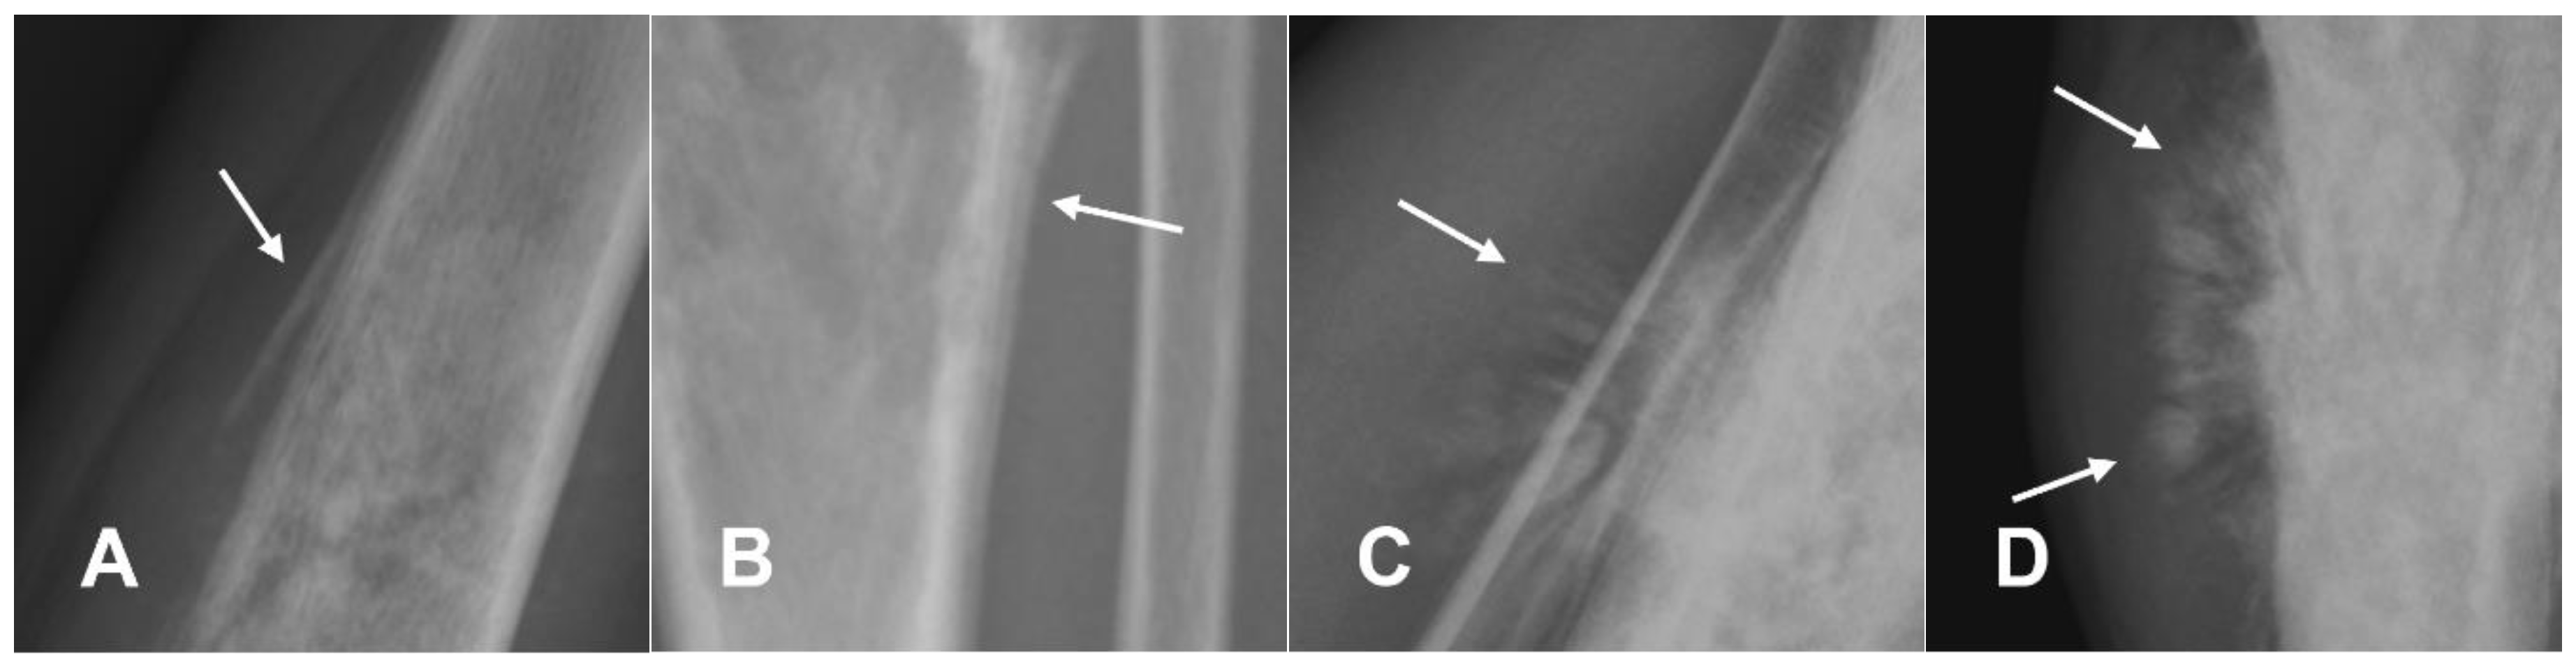

3.1.5. Low-Grade Central Osteosarcoma

- Andresen, K.J.; Sundaram, M.; Unni, K.K.; Sim, F.H. Imaging Features of Low-Grade Central Osteosarcoma of the Long Bones and Pelvis. Skeletal Radiol. 2004, 33, 373–379. [Google Scholar] [CrossRef] [PubMed]

- Choong, P.F.M.; Pritchard, D.J.; Rock, M.G.; Sim, F.H.; McLeod, R.A.; Unni, K.K. Low Grade Central Osteogenic Sarcoma A Long-Term Followup of 20 Patients. Clin. Orthop. Relat. Res. 1996, 322, 198. [Google Scholar] [CrossRef]

- Kurt, A.-M.; Unni, K.K.; McLeod, R.A.; Pritchard, D.J. Low-Grade Intraosseous Osteosarcoma. Cancer 1990, 65, 1418–1428. [Google Scholar] [CrossRef] [PubMed]